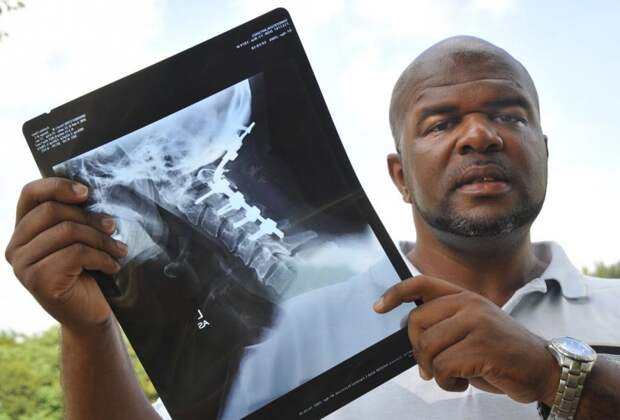

Внутреннее обезглавливание, также известное как ортопедическое обезглавливание. Череп как бы «снимается» от позвоночника, но всё остальное остаётся нетронутым. Вызывает немедленную смерть в 70% случаев